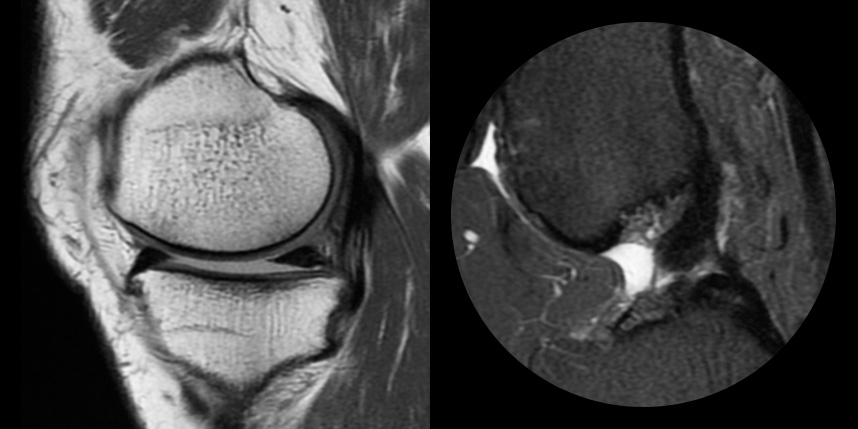

연골손상의 단계를 결정할 때 사용하는 ICRS 단계에서 3단계 미만의 연골손상에 사용하는 방법으로 울퉁불퉁한 표면을 다듬어 주는 정도의 수술법입니다.

4단계 이상일 경우 미세천공술을 기본으로 시행하며, 미세천공술로 나온 본인의 골수줄기세포와 함께

연골 생성을 촉진할 수 있는 “재료”를 같이 주입하는 치료를 시행합니다.

손상된 연골 부위에 작은 구멍을 뚫어 골수에서 나오는 줄기세포를 이용하여 연골 재생을 유도하는 방법으로 근본적으로 섬유연골(정상연골보다는 약한 연골)로 재생된다고 알려져 있습니다.

특수하게 농축하여 제작된 6% 콜라겐(리젠실603) 또는 9% 콜라겐(이엔카티)을 천공술을 시행한 부위에 덮어 주어 미세천공술 단독보다 좋은 치료 결과를 기대할 수 있습니다.

환자 자신의 건강한 연골을 채취하여 손상된 부위에 이식하는 방법으로, 발목 연골 손상에 주로 이용하며 정상 연골을 채취해야 하기 때문에 공여부(donor site)의 문제가 있을 수 있다는 점이 최대 단점입니다.